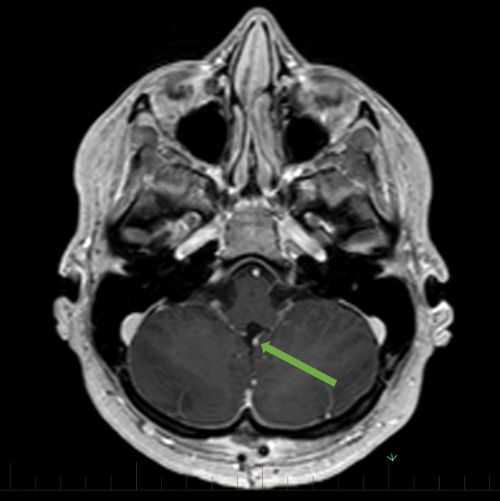

Signo Del Cerebelo Blanco

Signo Del Cerebelo Blanco O Signo Reverso Sciencedirect

Signo Del Cerebelo Blanco I Reversal Sign I Neurologia Com

El Signo Del Cerebelo Blanco O Signo Imagenologia Cuenca Facebook

Signo Del Cerebelo Blanco O Signo Reverso Neurologia Argentina